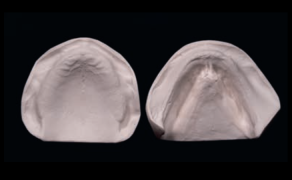

Pełna rehabilitacja protetyczna za pomocą wspartej na implantach protezy hybrydowej uzębienia szczęki z wykorzystaniem materiału wzmocnionego włóknami zamiast konwencjonalnego PMMA

- Niniejszy opis przypadku przedstawia wytwarzanie wspartej na implantach protezy hybrydowej uzębienia szczęki z wykorzystaniem kompozytu nanofilowego.

STRESZCZENIE: Wiele osób noszących protezy zębowe ma do końca życia problemy, takie jak trudności z mówieniem i jedzeniem, obluzowanie protez i zespół bólu jamy ustnej. Normalne zdrowe życie zapewnia tym pacjentom konstruowanie protez na implantach z racji ich zalet funkcjonalnych i estetycznych. Niniejszy opis przypadku przedstawia wytwarzanie wspartej na implantach protezy hybrydowej uzębienia szczęki z wykorzystaniem kompozytu nanofilowego (NFC) do budowy zębów w celu rehabilitacji protetycznej pacjentki, dotychczas używającej protezy całkowitej.

SUMMARY: Many people have life-long problems with their dentures, such as difficulties with speaking and eating, loose denture, and sore mouth syndrome. The evolution of dental implant supported prosthesis gives these patients normal healthy life for their functional and esthetic advantages. This case report presents the fabrication of maxillary implant supported hybrid prosthesis by using Nanofilled Composite (NFC) material in teeth construction to rehabilitate a complete denture wearer patient.